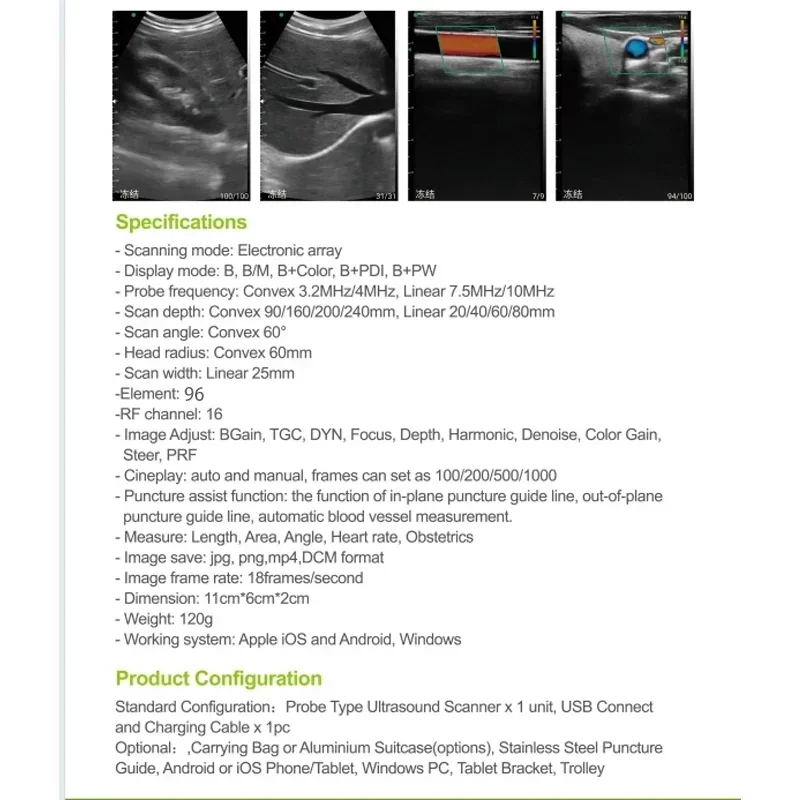

Linear Probe Parameters

-Scanning mode: Electronic array

-Display mode: B, B/M

-Probe element: 80

-Channel of RF circuit board: 16

-Frequency: 7.5MHz/10MH

-Scan depth: 20/40/60/100mm

-Head width: 40mm

-Image Adjust: BGain, TGC, DYN, Focus, Depth, Harmonic, Denoise, Color Gain, Steer, PRF

-Cineplay: auto and manual, frames can set as 100/200/500/1000

-Puncture assist function: the function of in-plane puncture guide line, out-of-plane puncture guide line, automatic blood vessel measurement.

-Measure: Length, Area, Angle, heart rate, Obstetrics

-Image save: jpg, avi and DICOM format

-Image frame rate: 18 frames / second

-Battery working time: 3~5 hours(according to different probe and whether keep scan)

Linear Probe Pictures:

This machine can be used for both humans and animals: